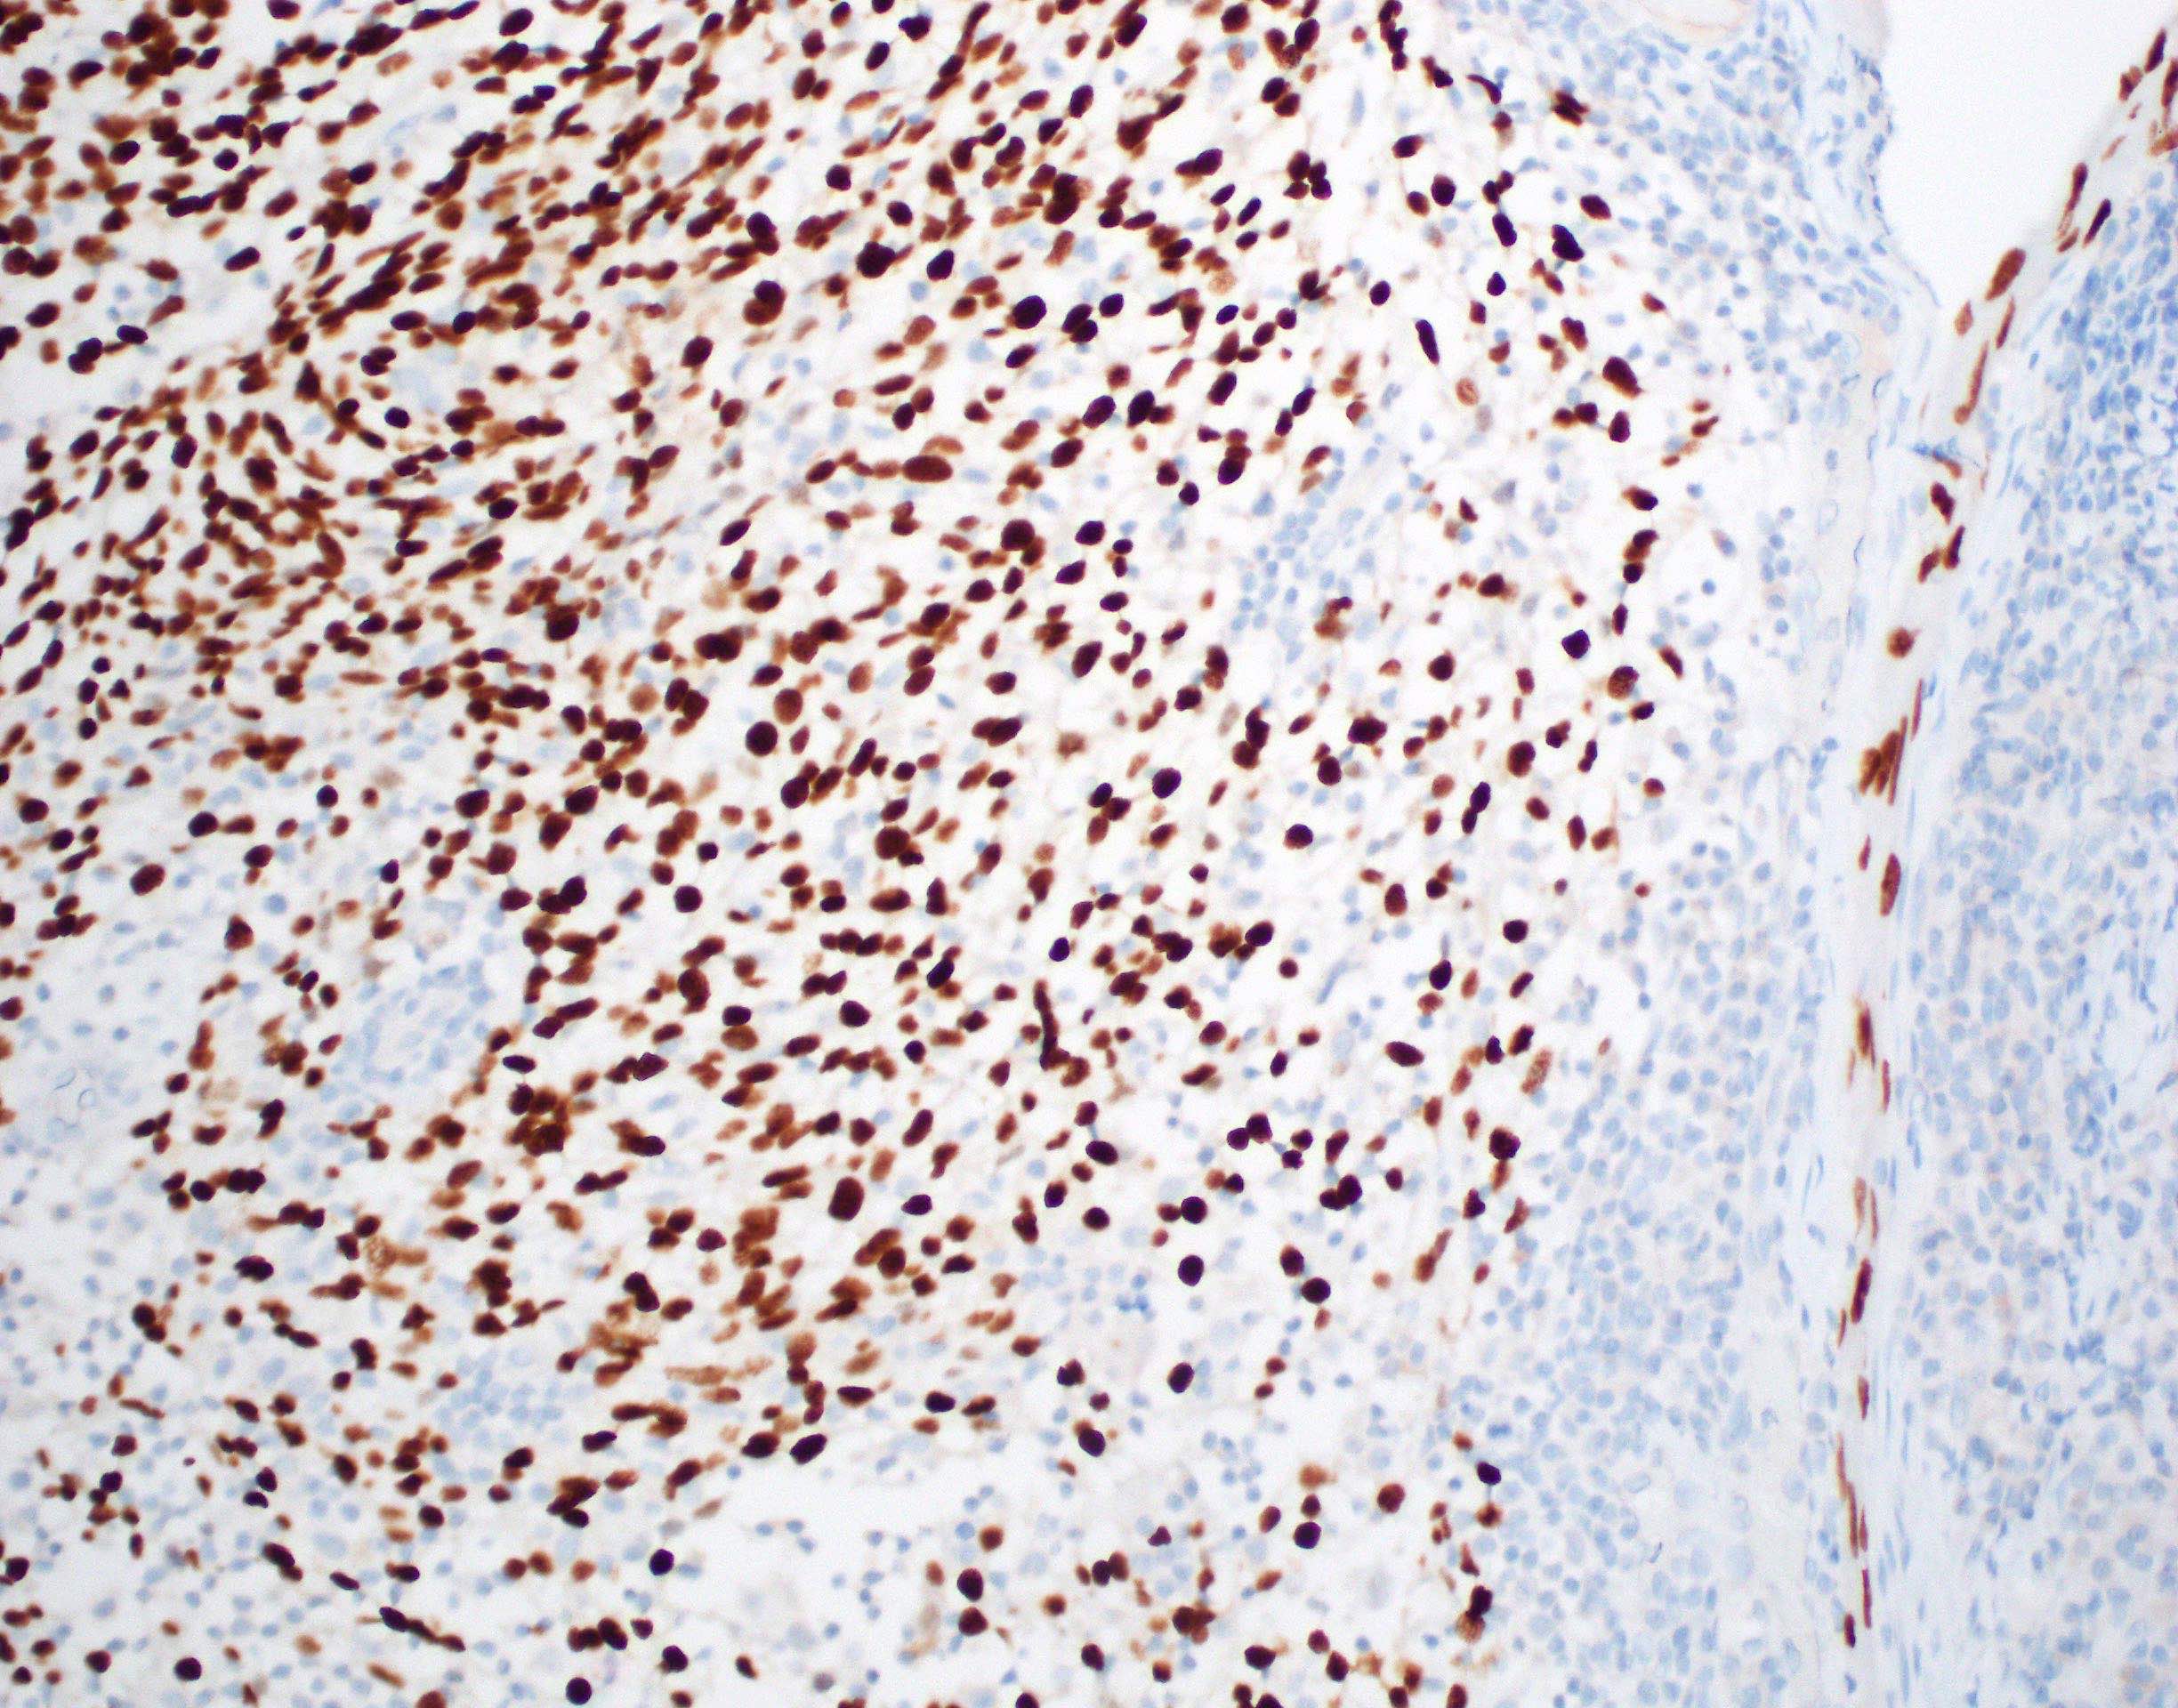

Microscopic (histologic) images

Contributed by Ruta Gupta, M.B.B.S., M.D.

Positive stains

- Diffusely and strongly positive:

Negative stains

Molecular / cytogenetics description

- Negative for presence of high risk HPV DNA / RNA

- EBV ISH negative

Sample pathology report

- Right soft palate and uvula and bilateral neck dissection levels I - IV, excision:

- Moderately differentiated squamous cell carcinoma (T = 28 mm, pT2) arising on a background of carcinoma in situ (see comment)

- Comment: Extensive perineural involvement is present. Local excision complete, closest margin: anterior mucosal 3 mm away. Bilateral neck dissection shows 2/66 lymph nodes with metastatic squamous cell carcinoma. The larger involved node is present in the right neck, measures 25 mm and shows extranodal extension (pN3b). AJCC 8th Ed pT2pN3b group stage 4. The tumor cells lack immunostaining with p16 excluding an HPV related oropharyngeal squamous cell carcinoma. HPV negative oropharyngeal squamous cell carcinoma is frequently associated with smoking and alcohol and does not carry the good prognosis described in HPV related oropharyngeal squamous cell carcinoma.